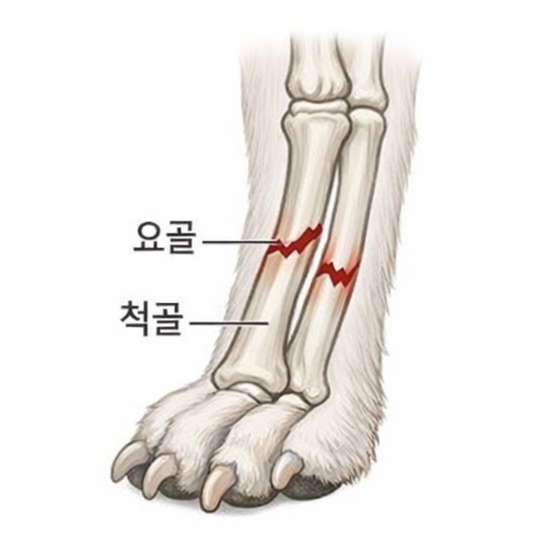

요척골 골절

앞다리를 구성하는 요골과 척골이 함께 또는 단독으로 부러지는 골절입니다. 소형견에서는 낙상 사고로 흔히 발생합니다.